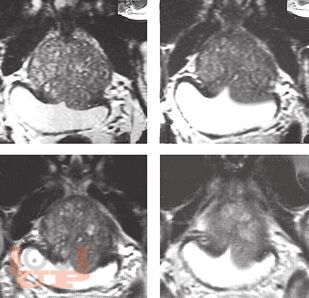

Возрастной андрогенный дефицит у мужчин

Возрастной андрогенный дефицит, несмотря на высокую распространенность, изучен недостаточно полно. Актуальность проблемы связана с тем, что дефицит андрогенов проявляется не только нарушением половой функции, но и ассоциирован со многими возрастными заболеваниями (ожирение, сахарный диабет, ИБС, остеопороз и др.), ухудшая их течение и прогноз.